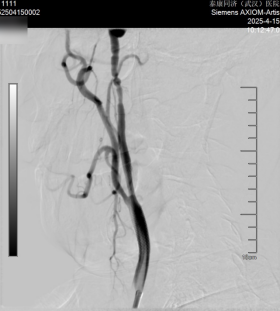

近日,張庭保教授團(tuán)隊(duì)為患者實(shí)施“右側(cè)頸內(nèi)動(dòng)脈球囊擴(kuò)張術(shù)+支架植入術(shù)+左側(cè)椎動(dòng)脈藥物球囊支架置入術(shù)”。術(shù)后腦血管造影顯示,右側(cè)頸內(nèi)動(dòng)脈及左椎動(dòng)脈狹窄情況明顯改善?;颊咝g(shù)后恢復(fù)良好,目前已康復(fù)出院。